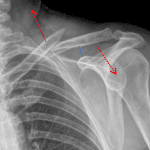

- Acute middle third left clavicle fracture with one shaft width inferior displacement of the distal fracture fragment and apex superior angulation

- Mild angulation at the left sternoclavicular joint without evidence of dislocation

Acute middle third left clavicle fracture with one shaft width inferior displacement of the distal fracture fragment and apex superior angulation.

Mild angulation at the left sternoclavicular joint without evidence of dislocation. Normal left acromioclavicular joint alignment. No widening of the coracoclavicular distance.

- The clavicle most commonly fractures at the junction of the middle and lateral thirds, in between attachments of the sternocleiodomastoid muscle medially and coracoclavicular ligament laterally

- When the fracture is complete, the medial fragment is typically pulled superiorly (and posteriorly) by the sternocleiodomastoid muscle while the lateral fragment is pulled inferiorly (and anteriorly) by the weight of the arm

- Always look for associated acromioclavicular joint malalignment or widening of the coracoclavicular distance (normal measurement < 13 mm)